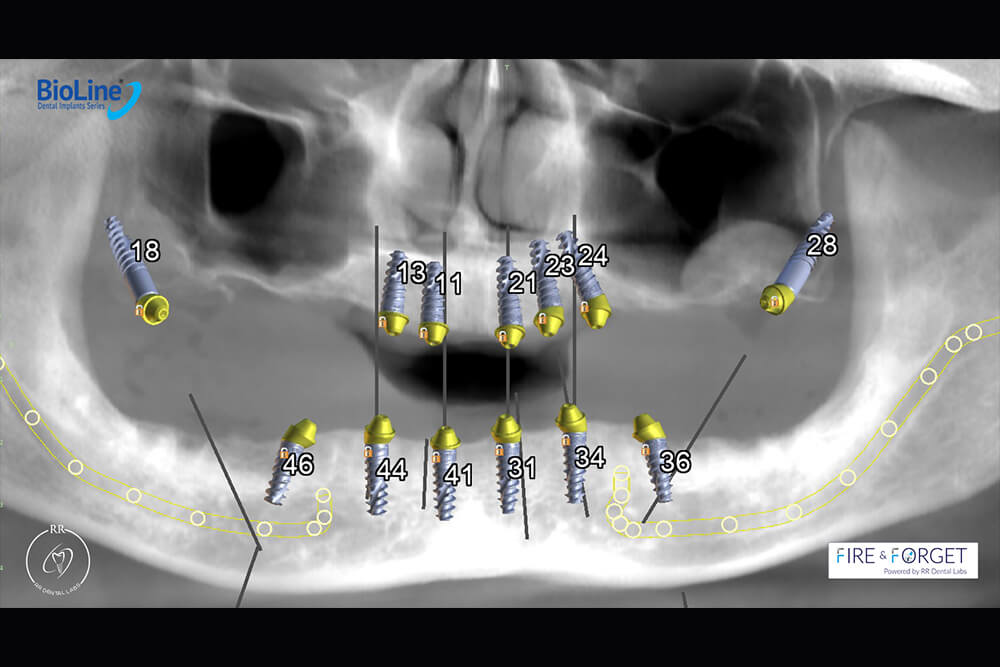

Case 47